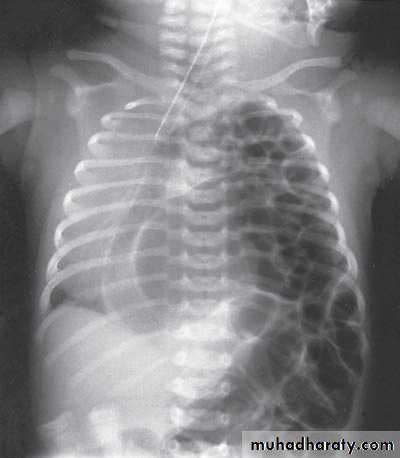

Second photo:

Diagnosis: congenital diaphragmatic hernia

Description: more dextrocardia – diaphragm not present – there is nasogastric tube

severe distress – very tired - 1 day age baby – more number of intestinal loops in

the chest - there is no lung tissue in the chest.

Treatment: pull the intestine ad close the hernia (through abdominal approach).